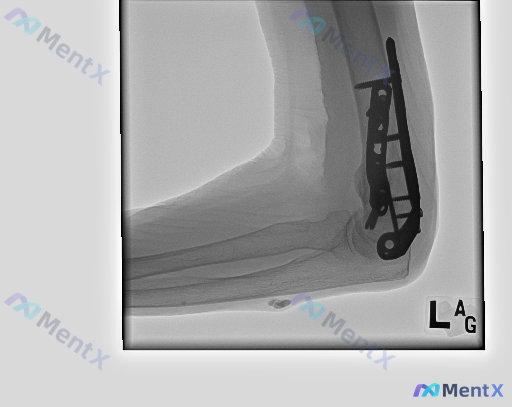

整理到一份左侧肘关节术后的影像资料,先把核心信息放出来,大家第一眼会怎么考虑? 背景:左侧肱骨远端骨折术后,复查侧位X光片(标记“L”)。 影像核心所见: 1. 肱骨远端可见金属接骨板+数枚螺钉内固定,钢板位置尚可,未见明显断裂/螺钉松动,可见骨愈合区域; 2. 肱尺、肱桡关节对位尚可,关节间隙无明...

整理到一张左侧肘关节的侧位X光片,先放核心影像所见,大家来聊聊思路: - 标注L,左侧肘关节侧位 - 肱尺、肱桡关节对位基本可,无明显脱位/半脱位 - 关键:桡骨头颈部可见高密度金属内固定物(微型螺钉类) - 前/后脂肪垫征阴性,无明显“帆船征” - 整体骨密度无弥漫异常,关节面尚平整,无明显急性骨...